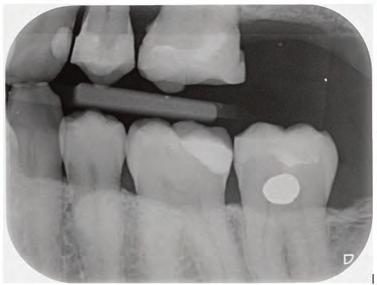

Clinical case

The patient was an 18-year-old male with a confirmed family history of Xlinked AI, who was otherwise in good health and non-smoking. Upon initial clinical presentation, a low-caries-risk, complete adult dentition from second molar to second molar was present, which was globally affected by pitted, hypoplastic and hypomineralised AI, dento-alveolar disproportion and an unusual generalised open occlusion, characterised by one occlusal contact at the right first molar region in the maximum intercuspation position (MIP). Historical paediatric management of the dentition involved placement of stainless steel crowns at the first permanent molar sites to protect the emerging dentition from post-eruptive breakdown and loss of occlusovertical dimension during the mixed dentition phase.6 On adult presentation, all but the UR6 stainless steel crown remained intact. Oral hygiene was poor, with evidence of plaque-induced chronic gingivitis (Figure 1). The patient reported experiencing severe, widespread hypersensitivity upon hot, cold, osmotic and masticatory stimuli, and feeling aesthetically self-conscious. The patient was seeking comprehensive fixed prosthodontic care and was well informed about the nature of such treatment, having witnessed his elder siblings undergo similar treatment.

1: The patient’s initial situation on clinical presentation to the tertiary care referral centre. The dentition is globally af fected by amelogenesis imperfecta, associated with dentoalveolar disproportion and an unusual presentation of open occlusion.